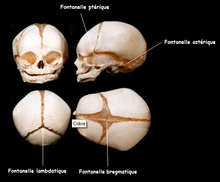

Its presence in a fetal skull, along with other cranial sutures and fontanelles, provides a malleability to the skull that can facilitate movement of the head through the cervical canal and vagina during delivery. The dense connective tissue found between the frontal bones is replaced with bone tissue as the child grows older.

| Human baby skull. Anterior view. |